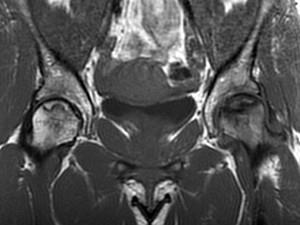

问题 女,34岁,双侧髋部疼痛,结合图像,最可能的诊断是 ( )

选项 A、股骨头缺血坏死 B、痛风 C、类风湿关节炎 D、髋关节退行性变 E、未见异常

答案 A